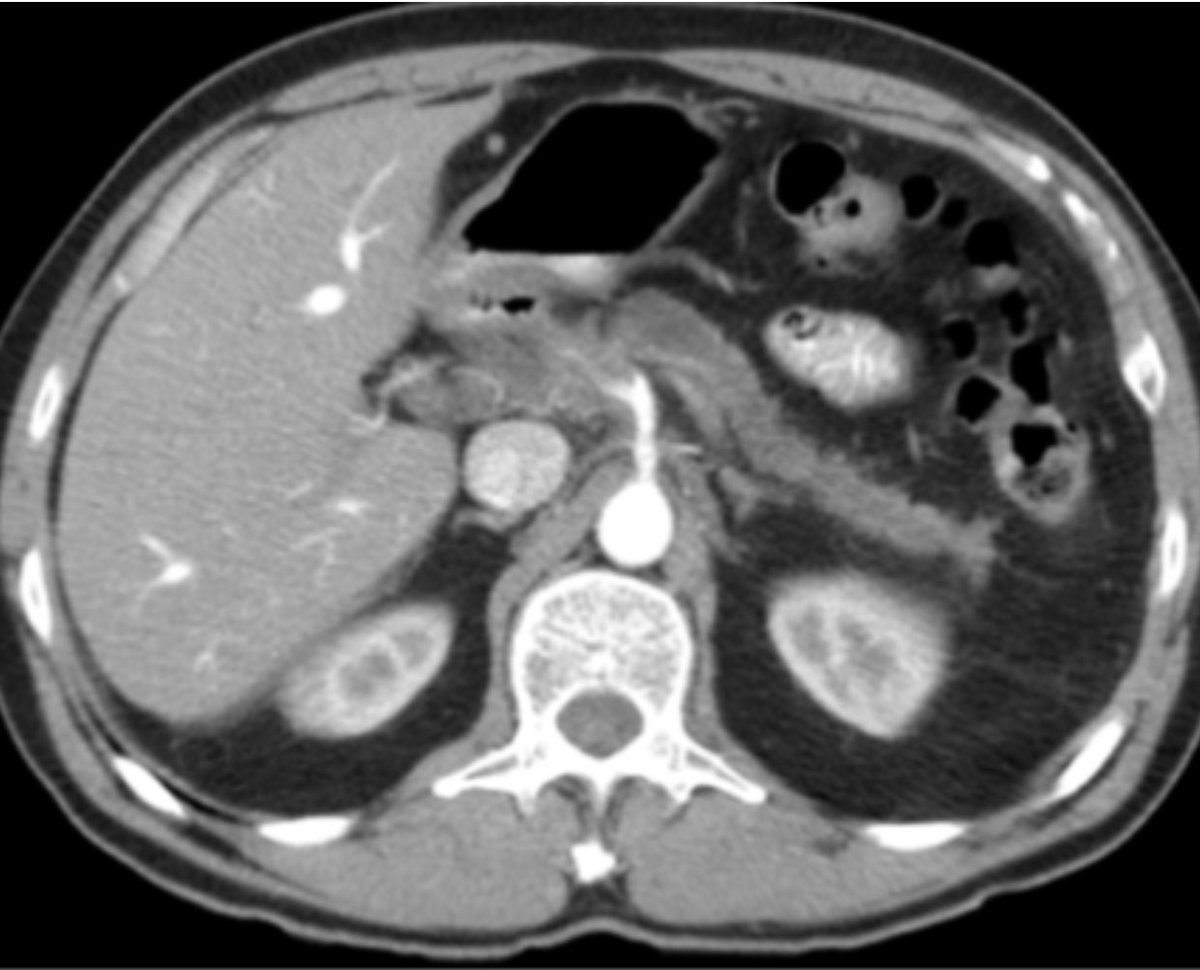

Ct Scan Missed Cancer. Thanks for the coment ,ive always felt like the ct scan missed what the problem was, i mean i went down the list of symptoms from chronic pancreatitis and panc cancer, and it was 6 for yes and 1 for no on cp and it was 4 yes and 4 no for panc cancer, not that u can go,oh u have cp ,because of that,but ive been having these symptoms since june 6th 2013,my gi doctor 1st. The defendants were prepared to argue that the nodule, which was seen in 1991 and 1992 on the ct scan, was not cancer.

Then you can ask your doctor more directly about what it shows. Malpractice cases involving missing lung cancer on chest ct are well demonstrated. My private consultant says if the pains im having were from pancteatic cancer it would be advanced and they would definitely have seen something on.

• peritumoural findings and shorter tumour length contribute to failure of detection. Repeated cts, however, can increase your risk over time. Ct scans are sometimes referred to as cat scans.

Have no signs or symptoms of lung cancer; Therefore, ct scans can lead to a false negative; Of these, 8% (12/150) had false negative results.

Having had a clear xray and a ct scan showing 'nothing of significance'' i am still struggling with high levels of anxiety worrying that the ct scan missed a lung tumour. Imaging tests usually can’t tell if a change has been caused by cancer. Only a ct scan or an mri scan will give you a good idea of whether or not the cancer has spread elsewhere.

Thanks for the coment ,ive always felt like the ct scan missed what the problem was, i mean i went down the list of symptoms from chronic pancreatitis and panc cancer, and it was 6 for yes and 1 for no on cp and it was 4 yes and 4 no for panc cancer, not that u can go,oh u have cp ,because of that,but ive been having these symptoms since june 6th 2013,my gi doctor 1st. This can negatively impact your ability to get any treatment at all; The false negative rate for crc diagnosis was 3.5% for colonoscopy (3/85), 6.7% for ctc (1/17), 9.4% for ct (5/53), and 26.7% for dcbe (4/15).